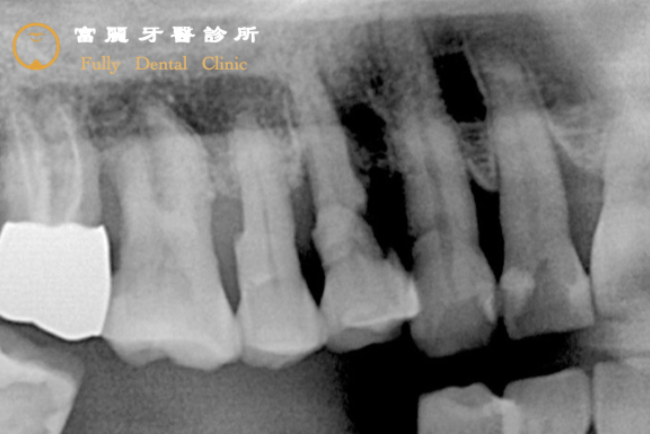

Before

包覆牙根的骨頭(灰色網狀)在最後一顆大臼齒的位置被細菌破壞得非常嚴重(黑色的範圍),缺少骨頭支撐的牙齒會開始出現晃動,當骨頭被破壞得範圍愈來愈大,牙齒便會整顆脫落。晃動所造成咀嚼能力的下降,讓患者決定以植牙來恢復!